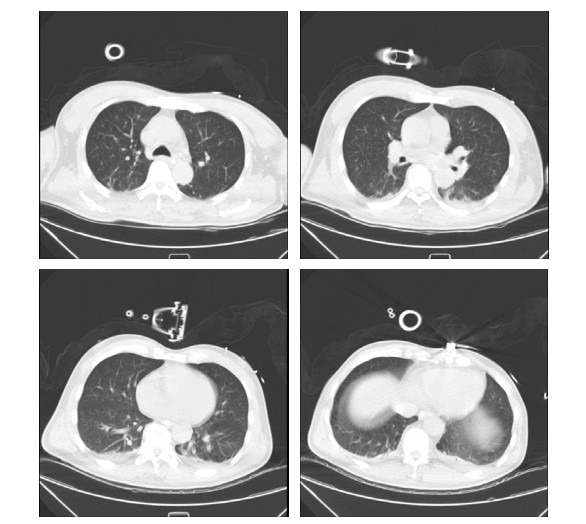

患者男性,58岁,因“头晕、黑矇3 d,意识不清15 h”于2021-07-07 18:53急诊以“意识障碍待查”收入本院重症医学科。患者3 d前无明显诱因出现头晕、黑矇,共发作7~8次,每次持续5~10 min后自行缓解,上述症状与体位无关,不伴有头痛、耳鸣、视物双影及视物旋转,无发热,曾于当地医院就诊考虑“眩晕症”,给予静点川芎嗪及血栓通后上述症状有所缓解。于入本院前15 h如厕时被家属发现倒地,呼之不应,无抽搐发作,无尿便失禁,无舌咬伤及呕吐,急由120救护车送至当地医院,测体温42.0℃(距离发病1 h),行头部及肺部CT未见明显异常,肝肾功能及降钙素原结果均正常,为求明确诊疗转诊至本院,急诊以“意识障碍待查”收入重症医学科。病程中无咳嗽、咳痰,无尿急、尿频、尿痛,无恶心、呕吐,无腹痛、腹泻。既往史情况:发现高血压病史1年,血压最高160/80 mmHg(1 mmHg=0.133 kPa),未系统诊治及监测。脑梗死病史1年。吸烟史20年,约10支/d,未戒。饮酒史20年,约100 g/d,戒酒1年余。入科查体:体温39.1℃,脉搏114次/min,呼吸23次/min,血压129/80 mmHg,外周血氧饱和度98%(鼻导管吸氧,氧流量3 L/min)。意识不清,GCS评分5分,双侧瞳孔等大同圆,直径约4.5 mm,直接、间接对光反射迟钝,皮肤、巩膜无黄染,咽部无红肿,扁桃体无肿大,气管居中,听诊双肺呼吸音清,未闻及干湿啰音。心率114次/min,律整,各瓣膜听诊区未闻及杂音及额外心音。腹软,肝脾肋下未触及,肠鸣音3~4次/min。双下肢无水肿,项强征阴性,双侧babinski征阳性,kernig征阴性,余查体不配合。辅助检查(2021-07-07,当地医院),血常规:WBC 12.3 × 109/L, NE% 67.6%,PLT 245 × 109/L,PCT 0.18 ng/mL, 肌酸激酶420 U/L,感染标志物:乙肝(−),丙肝(−),肝功能:AST 50 U/L,ALT 40 U/L, 入科诊断:意识障碍待查、发热原因待查。入科后给予降温、促醒对症治疗,约6 h后体温降至38.5℃,但患者意识无恢复,无自主咳痰能力,双肺可闻及痰鸣音,于2021-07-08给予气管插管及呼吸机辅助通气,同日出现血压下降,给予补液、升压(去甲肾上腺素)对症治疗。入科后进一步完善相关检查包括,出血热抗体:阴性,呼吸道病原核酸检测:阴性,IL-4 4.05 pg/mL,IL-6 229 pg/mL,IL-10 22.90 pg/mL,肌酸激酶13 383 Μ/L,肌红蛋白4 077 ng/mL;血栓弹力图:R 10.8 min,MA-CK 21.4 mm,K 23.4 min,综合凝血指数-19.9;肝功能:AST 2 643.0 M/L,ALT 2 711.9 M/L,ALB 32.1 g/L,TB 142.5 μmmol/L,DB 85.1 μmmol/L,CB 57.4 μmmol/L;肾功能:Scr 94.3 μmol/L、BMN 7.1 mmol/L;血常规及凝血相关指标变化见表 1;头部CT提示双侧小脑半球、脑干、双侧枕叶、丘脑、放射冠、半卵圆中心低密度影(图 1);肺部CT提示支气管炎、双肺散在炎症、胸主动脉及冠脉动脉硬化(图 2)。综合病史、体征和辅助检查明确临床诊断为:椎基底动脉脑梗死、中枢性高热、多器官功能障碍综合征(循环、肝脏、血液)、横纹肌溶解综合征,给予脱水降颅压、营养神经、促醒、纠正凝血异常对症治疗,患者病情无好转,于2021-07-09家属放弃治疗,出院后死亡。

图 2 2021-07-09患者肺部CT